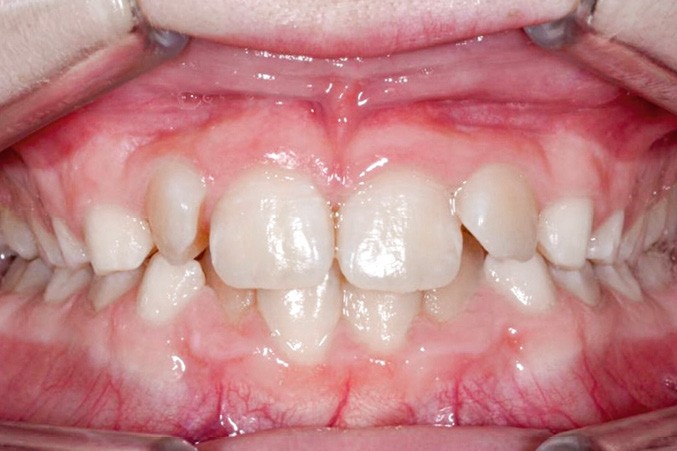

Un appareil multi-attache est mis en place avec une prescription MBT en .022 x .028. une fois les faces vestibulaires des canines maxillaires apparentes. 13 et 23 ne sont pas prises en charge dans l’arc pour éviter les effets parasites sur les dents adjacentes. Leur traction est poursuivie avec des élastiques de Classe II (1/4” – 3.5 oz) en port nocturne. Ces élastiques sont portés sur un bouton palatin pour la 23 afin de corriger sa rotation mésio-vestibulaire. Une fois les canines suffisamment proches du plan occlusal, elles sont prises en charge dans un arc continu en suivant les séquences suivantes : .014, .018 et .019 x .025 Niti. Une fois l’arc .019 x .025 en Niti en place pendant huit semaines, l’arc transpalatin est déposé. L’arcade mandibulaire suit cette même séquence d’arcs avec l’ajout d’un arc en acier .019 x .025 avec courbe de Spee inversée pour aider à la correction de la supraclusion.

À ce stade, une radiographie panoramique est réalisée pour s’assurer de l’intégrité des racines, contrôler les axes dentaires et planifier le repositionnement de certaines attaches ainsi que le collage des tubes sur les secondes molaires en cours d’éruption.